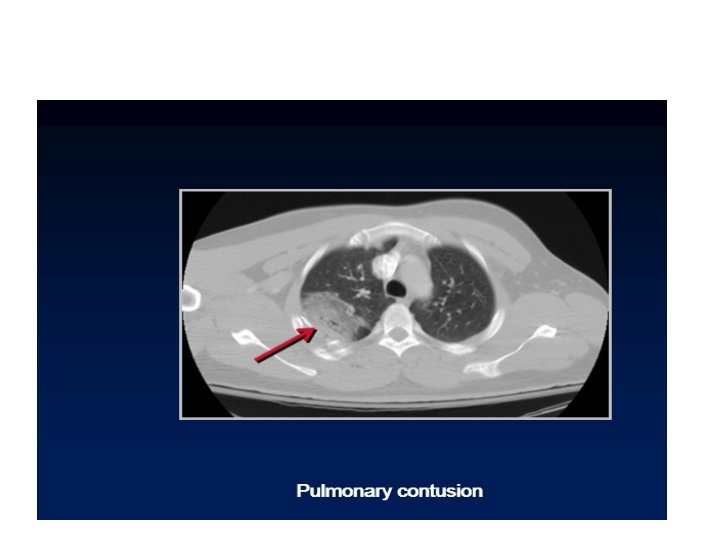

Pulmonary contusion

contusion • Disruption of the micro- scopical architecture of the lung with hemorrhage in

contusion • Disruption of the micro- scopical architecture of the lung with hemorrhage in the alveoli as a result of damage to capillaries. This will interfere with gas exchange leading to hypoxia , it dose not involve tear or cut of the lung tissue

Pulmonary contusion may mask pulmonary laceration on plain chest film. . Associated flail chest

Pulmonary contusion may mask pulmonary laceration on plain chest film. . Associated flail chest and sub cut. Emphysema